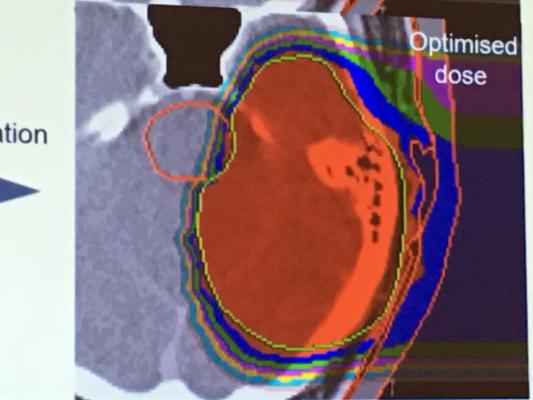

Comparison Of Dose Distribution For A Patient With Low Grade Glioma A Download Scientific Diagram